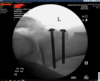

Next. I used intra-operative fluoroscopy to localize my tibial tubercle transfer. My goal was to elevate -1-2cm and medialize 1-2 cm. I measured this intra-operatively then placed two Steinman pins proximally and distally in the tibial tubercle graft through the posterior cortex. I was then able to use fluro and Measure the screw distances. The screws, in sizes of 5 so I found the appropriate screws, added a washer. The screws are self-tapping so use power then and to ensure excellent compression at the ostomy site. I then used fluoroscopy to confirm appropriate hardware localization. Tourniquet time was 65 minutes with an estimated blood loss of 20 mL.